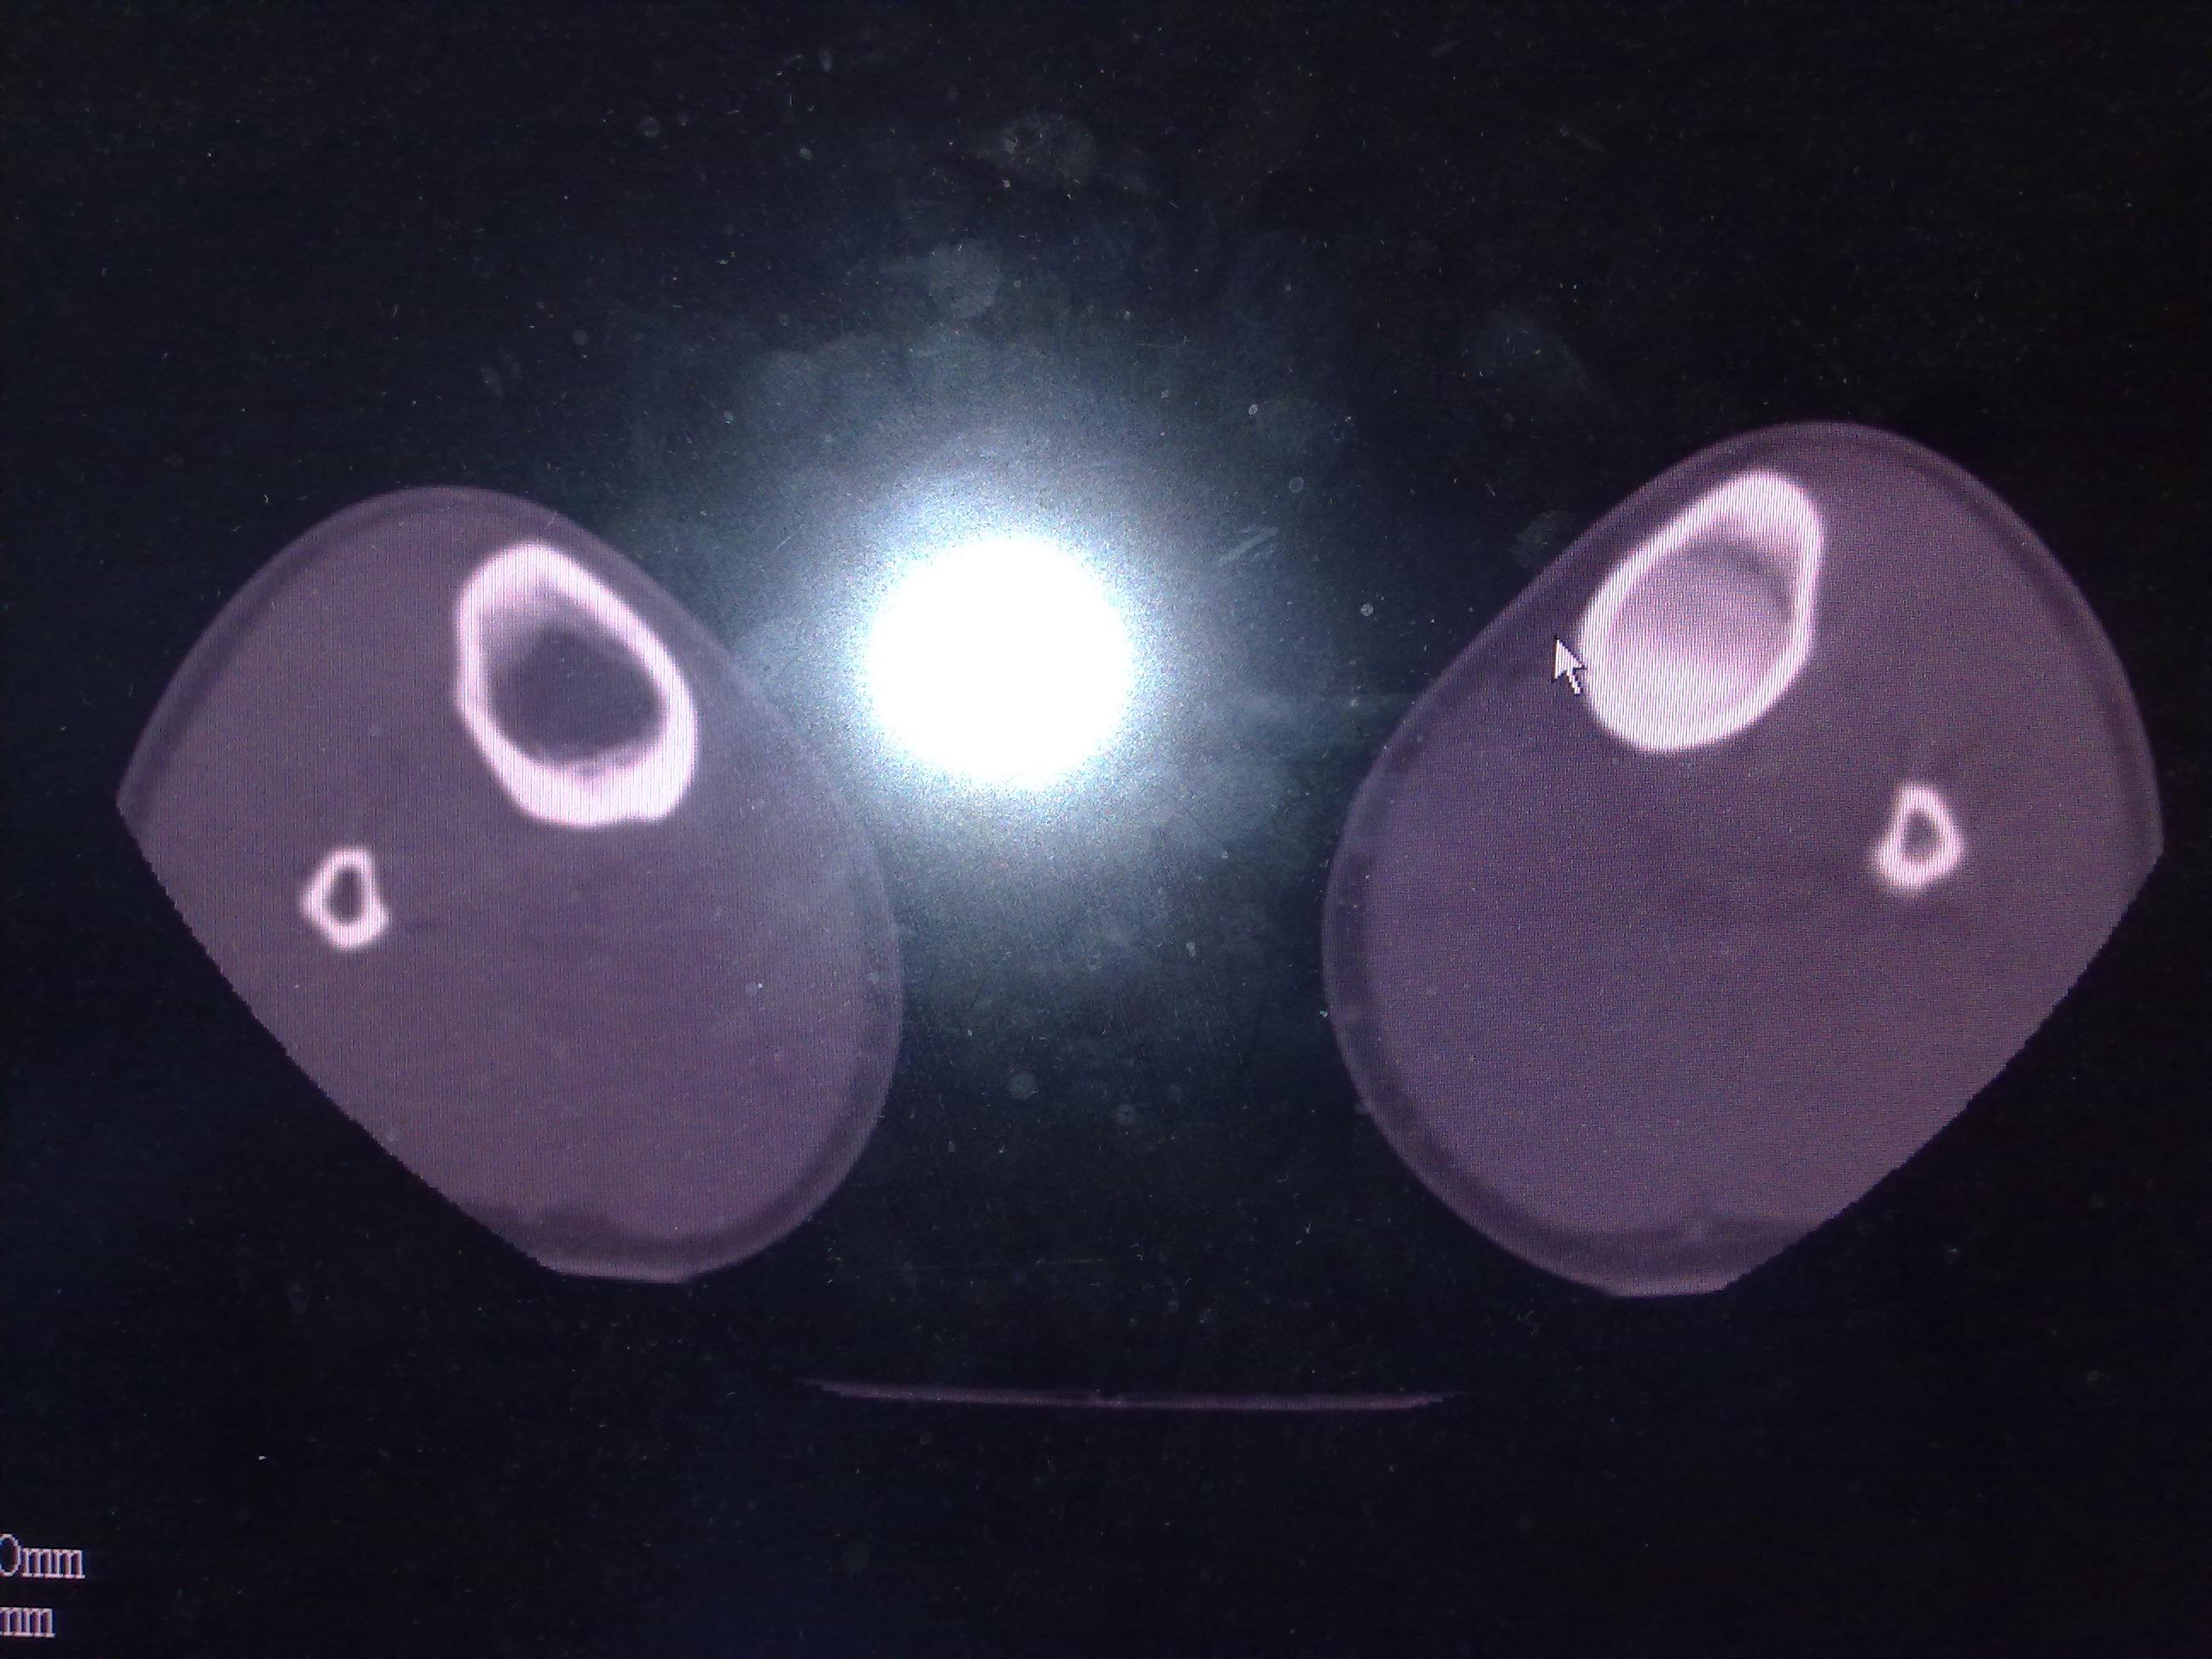

骨内骨软骨瘤?

图片尺寸2592x1944